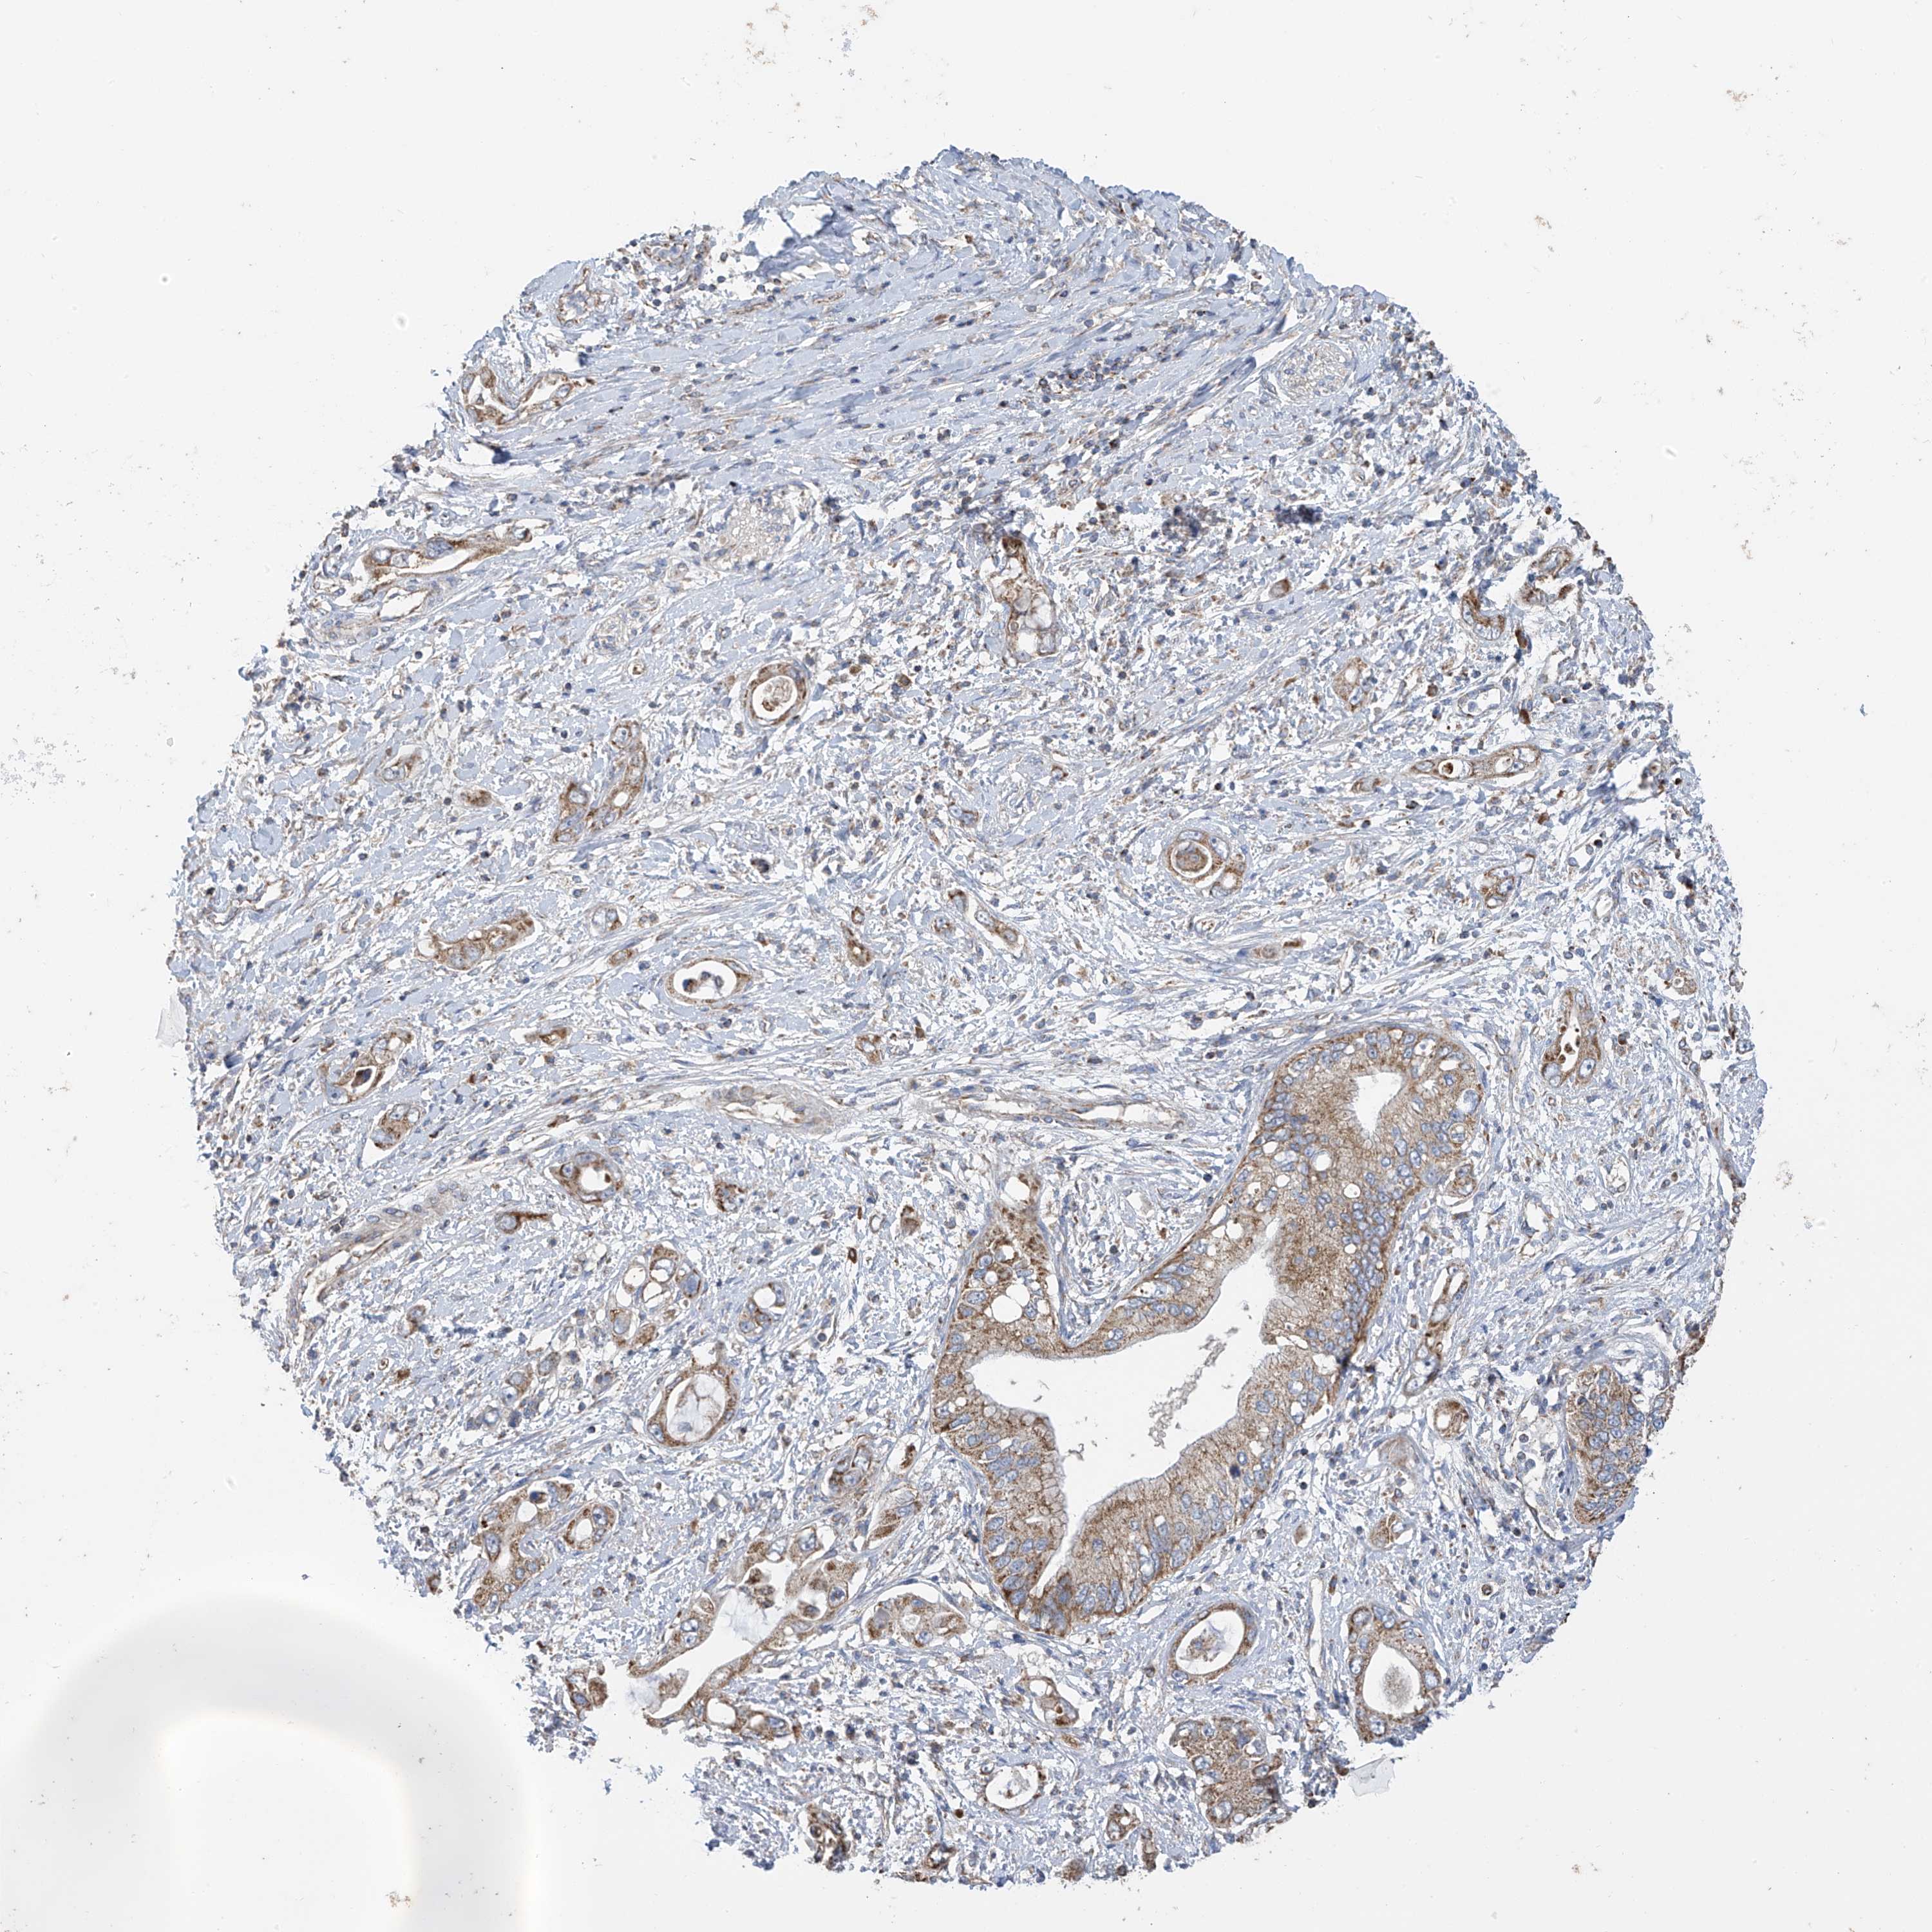

PANCREATIC CANCER - Protein expressioni

A mouse-over function shows sample information and annotation data. Click on an image to view it in a full screen mode. Samples can be filtered based on level of antibody staining by selecting one or several of the following categories: high, medium, low and not detected. The assay and annotation is described here.

Note that samples used for immunohistochemistry by the Human Protein Atlas do not correspond to samples in the TCGA dataset.

Antibody stainingi

Antibody staining in the annotated cell types in the current human tissue is reported as not detected, low, medium, or high, based on conventional immunohistochemistry profiling in selected tissues. This score is based on the combination of the staining intensity and fraction of stained cells.

Each image is clickable and will lead to virtual microscopy that enables deeper exploration of all samples and also displays staining intensity scores, fraction scores and subcellular localization as well as patient and tissue information for each sample.

Antibody HPA034602

Antibody HPA034603

Antibody CAB033424

Staining

High

Medium

Low

Not detected

Intensity

Strong

Moderate

Weak

Negative

Quantity

>75%

75%-25%

<25%

None

Location

Nuclear

Cytoplasmic/membranous

Cytoplasmic/membranous,nuclear

Adenocarcinoma, NOS